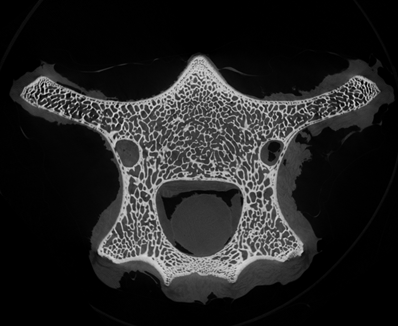

小編很好奇在micro CT掃描中,這些笑臉會是什么樣子?我們選擇了一段羊的脊椎骨放入CT設備中進行掃描,在得到的幾百張切片圖中,挑選出一張“萌萌的大笑臉”。

Step1. 獲得CT三維體數據

骨骼CT切片圖